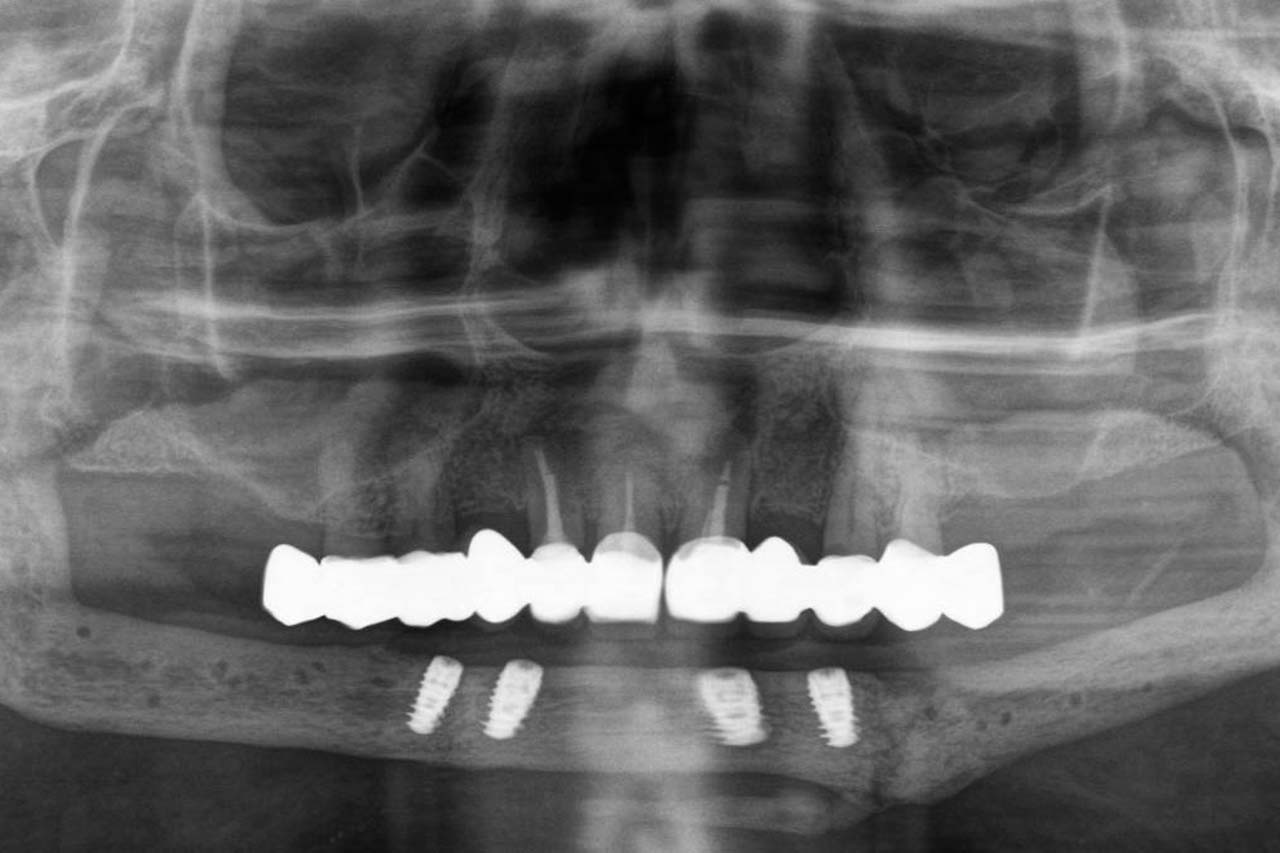

Nutzen des digitalen Workflows bei der prothetischen Rekonstruktion kompromittierter und gesunder Patienten

Prof. Dr. Dr. Walter Lückerath, Bonn

„Implantatprothetik – Unterschiede zwischen kompromittierten und gesunden Patienten“

Prof. Dr. Sven Reich